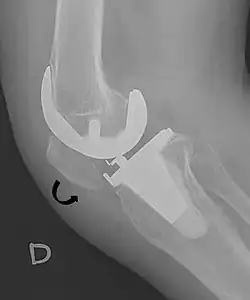

A patella baja is a low-riding patella. A long-standing patella baja may result in extensor dysfunction.[6]

The Insall-Salvati ratio helps to indicate patella baja on lateral X-rays, and is calculated as the patellar tendon length divided by the patellar bone length. An Insall-Salvati ratio of < 0.8 indicates patella baja.[7]